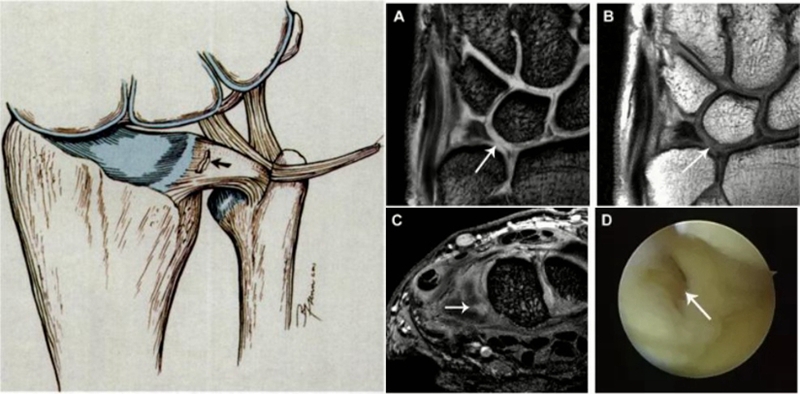

ⅠB,TFCC尺侧撕裂;TFC尺侧附着处信号增高

ⅠC,尺三角韧带撕裂